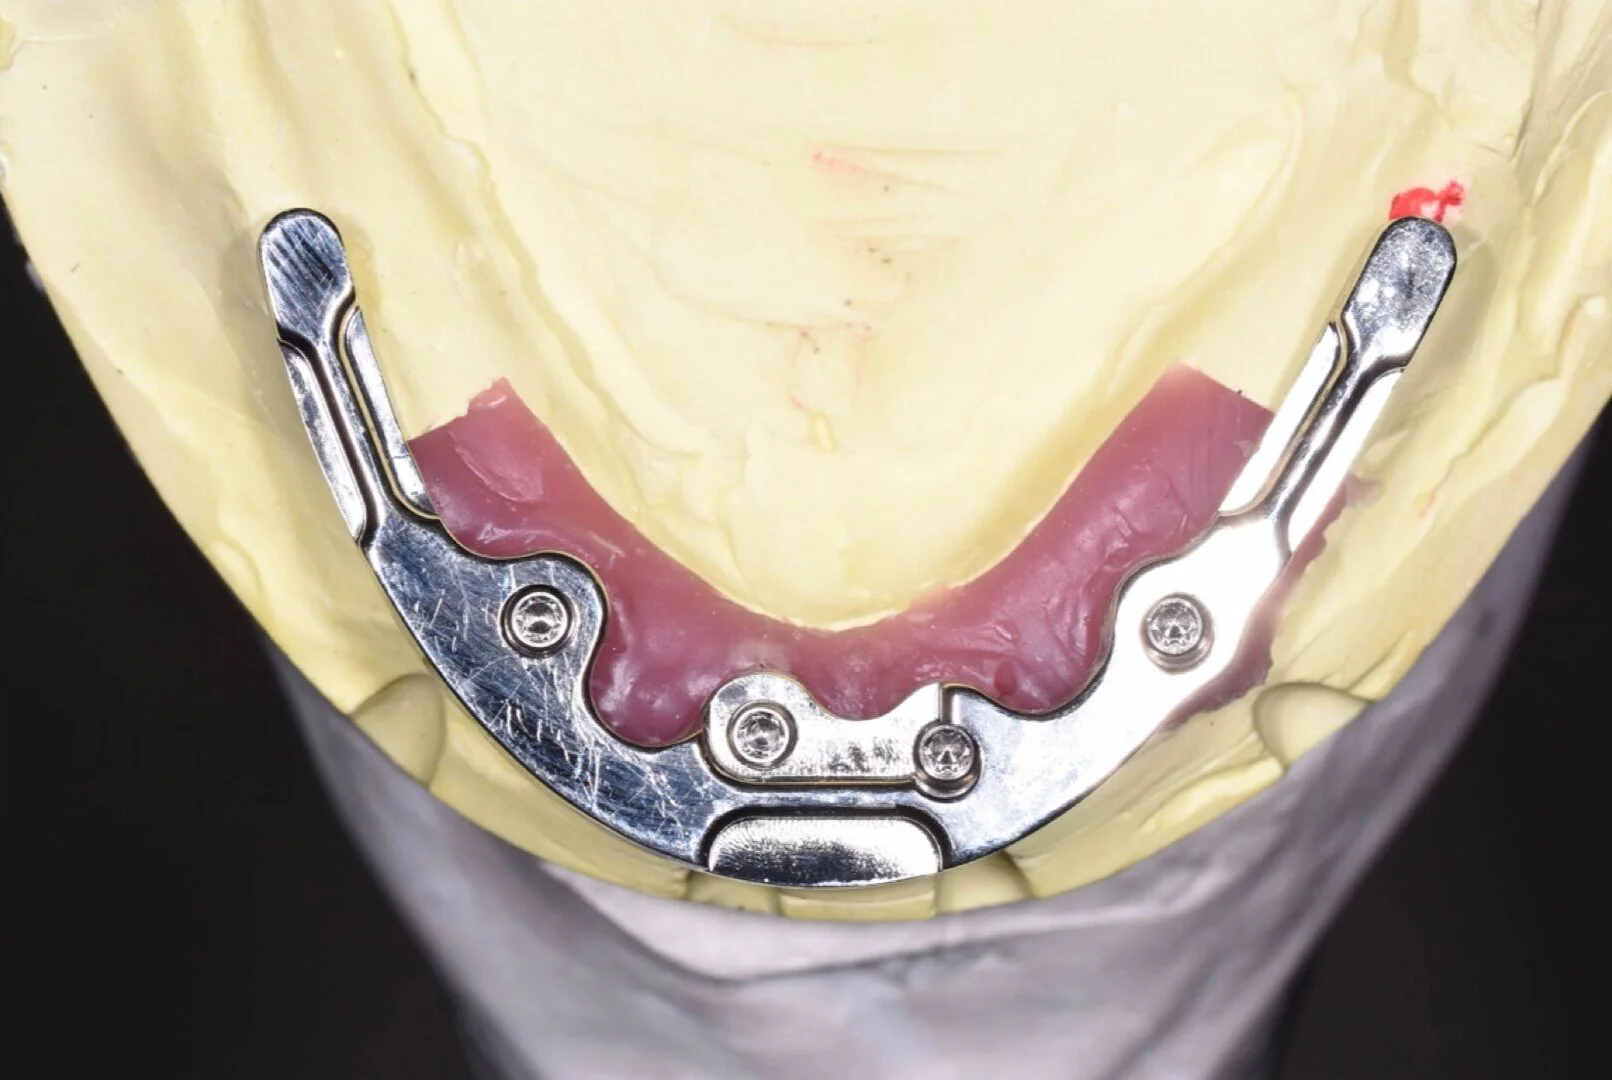

• Bar design

• Attachment choice and design

• Optimising the occlusal scheme

• Mucosal- and implant-borne removable prostheses